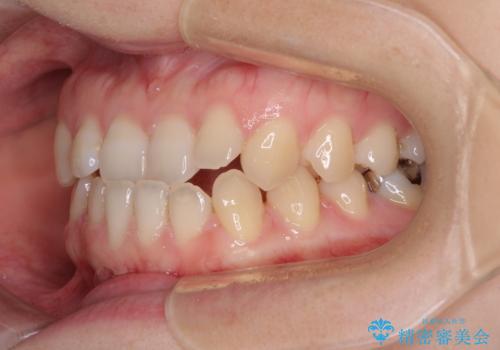

前歯のクロスバイト インビザラインによる矯正治療

- 前歯のクロスバイトとデコボコを気にして来院された患者様です。

骨格的に下顎前突傾向であるため、自己管理が煩わしくないようであれば、インビザラインによる矯正治療がお勧めとなります。

インビザラインを用い、下顎歯列を後方に移動させながら全市の被蓋を改善し、歯並びを整えていくこととしました。

途中マウスピースが使用できず、来院されない期間があり、治療期間は長くかかりましたが、無事に治療を終えることができました。